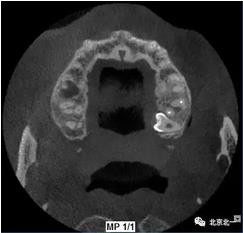

圖三:橫斷面可見(jiàn)智齒水平橫向腭側(cè)。完全骨埋伏。